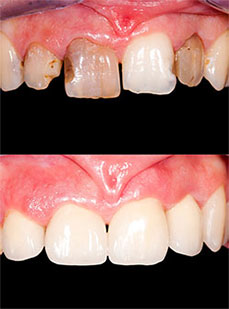

A chipped front tooth or gaps between teeth can be very distracting to an otherwise great smile. Dark spots, staining or uneven sized teeth may diminish confidence.

Good news, these are all potentially solved in one or two visits. In most cases, white filling materials (composite resin bonding) that are matched to the shade of your teeth can fill these chips, gaps and defects, all in a single visit. Sometimes referred to as “instant orthodontics”, white fillings fill voids, reshape teeth, and even bring teeth into alignment for an instant smile improvement. For larger chips, gaps, or defects, perhaps veneers or crowns may be indicated.

Veneers are thin porcelain shells that are bonded to the fronts of teeth, while caps or crowns cover over the entire tooth. Veneers are recommended when most of the tooth is not restored, while crowns are recommended when a lot of the natural tooth structure has been lost.

Veneers and crowns are more expensive than white fillings and may take a couple more appointments (although, with our innovative Nevo™ system, many crowns at the back of the mouth are done in one appointment). They are stronger, more color stable, and provide better esthetics. And for the difficult staining cases resistant to simple whitening, veneers and crowns are little miracles!